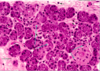

sinusoidal capillaries

what we call sinusoidal capillaries that are found at either side of hepatocytes (2).